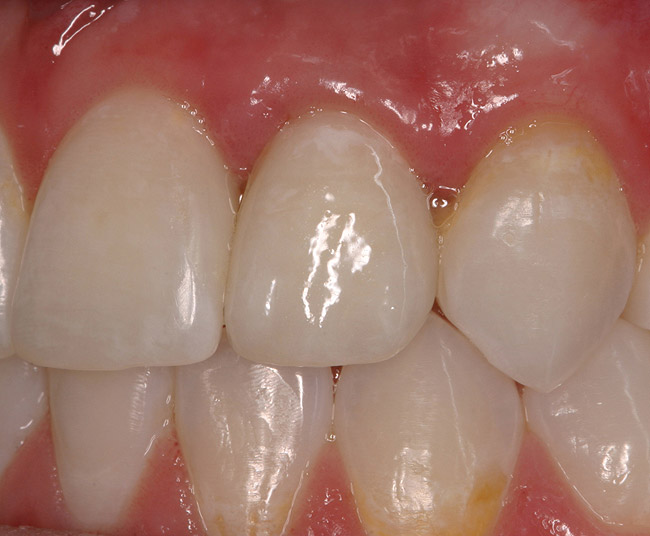

Figure 6a  Upper right central incisor, history of trauma, existing RCT and restoration unsatisfactory.

Figure 6a

Figure 6b  Upper right central incisor, history of trauma, existing RCT and restoration unsatisfactory.

Figure 6b

Figure 6c  Upper right central incisor, history of trauma, existing RCT and restoration unsatisfactory.

Figure 6c

Figure 6d Completed treatment: revised RCT, zirconium post/pressed ceramic core cemented with Panavia 21¬Æ Resin Cement (Kuraray Dental). All-ceramic full-coverage crown cemented with Kerr NX3 Nexus¬Æ Third Generation Dual Cure Resin cement. Implant therapy not indicated.

Figure 6d

Figure 6e  Completed treatment: revised RCT, zirconium post/pressed ceramic core cemented with Panavia 21¬Æ Resin Cement (Kuraray Dental). All-ceramic full-coverage crown cemented with Kerr NX3 Nexus¬Æ Third Generation Dual Cure Resin cement. Implant therapy not indicated.

Figure 6e

Figure 6f  Completed treatment: revised RCT, zirconium post/pressed ceramic core cemented with Panavia 21¬Æ Resin Cement (Kuraray Dental). All-ceramic full-coverage crown cemented with Kerr NX3 Nexus¬Æ Third Generation Dual Cure Resin cement. Implant therapy not indicated.

Figure 6f

De Backer et al19 recently evaluated data collected over a 16- to 20-year period from the undergraduate dental clinics at Ghent University, Belgium. For the single-crown group, similar survival rates were found in vital (74.9%) and root canal treated (RCT) groups (79.4%) (Figure 6). At 20 years, the FPD was 77.4% for the vital group and 56.7% when at least one of the abutments had root canal therapy. The authors concluded that “for FPDs with more than 3 units and cantilever FPDs, the use of a post-and-core abutment led to significantly more failures.” These conclusions were also supported by Tan et al.20

When evaluating the data presented on FPDs, certain conclusions can be made. FPDs have short lifespans after 10 years, with caries and endodontic problems the primary cause of failure.8,23-25 Once a complication occurs, the failure of FPDs often results in the loss of abutment teeth and the need for additional abutment teeth and pontics. Also, FPD retainer crowns/abutments have lower survival rates than single (non-splinted, stand-alone, tooth-borne) crowns.8,18 RCT FPD abutment teeth have significantly lower success rates than non-RCT-abutments or single crowns.19,20 With single crowns, RCT single crowns (Figure 6) have a similar survival rate as non-RCT crowns.19,20